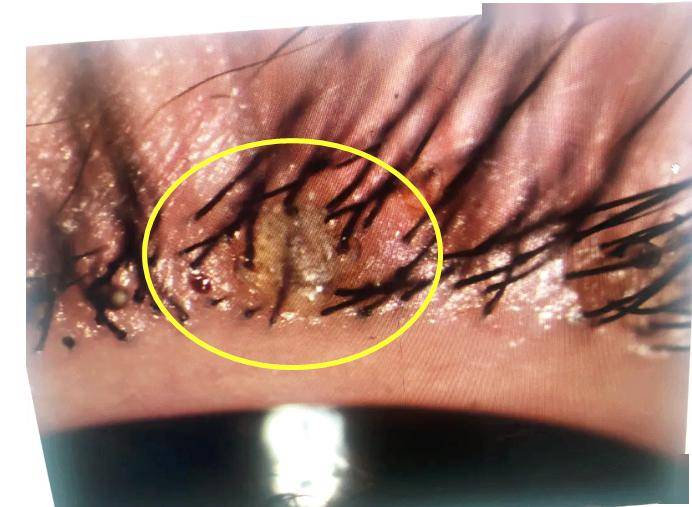

眼睑缘炎

睑缘炎

眼睑缘炎的原因及治疗

分泌物增多,或是眼睑缘充血,肿胀,有鳞屑等,这很有可能是患上了睑缘炎